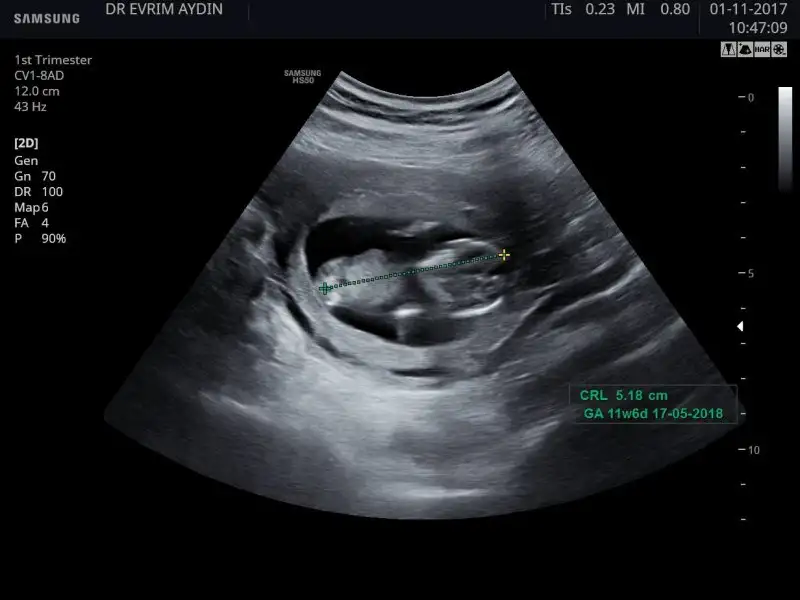

Haftaya ikili test icin cagirdilar ona gidecem. Insallah canim ya sivi aldirmayi asla dusunmuyorum zaten, herseyin hayirlisi olsun cok sukur korktugum kadar yuksek cikmadi. Bazilarinda 4 mm felan okuyordum bizim 2.63 mm cikti ama net olcumler icin aslinda 12 haftayi bekliyorlarmis. Biraz doktorumun abartmasi beni korkuttu sanirim.